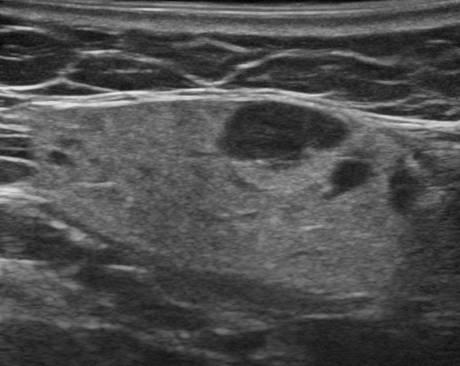

Hạch tuyến nước bọt

» Thông tin: Nữ giới – 66 tuổi.

» Lâm sàng: Sưng đau vùng góc hàm.

# Hạch lành tính ngoại vi tuyến nước bọt dưới hàm.